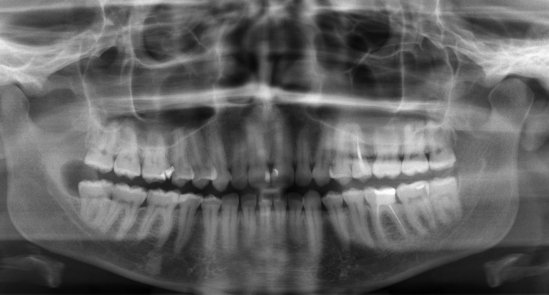

Здравствуйте! Есть ли у меня киста? Если да, то как срочно нужно делать операцию и как она называется?

Какой зуб вы имеете ввиду? Уточните. 18 и 48 зуб необходимо удалить. Далее расскажу после уточнения.